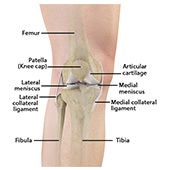

The joint surface is covered by a smooth articular surface that allows pain-free movement in the joint. Arthritis is a general term covering numerous conditions where the joint surface or cartilage wears out. This surface can wear out for several reasons; often the definite cause is not known. Arthritis often affects the knee joint. When the articular cartilage wears out, the bone ends rub on one another and cause pain. The most common type of arthritis is osteoarthritis. It occurs with aging and use.

Patellofemoral arthritis is an inflammatory condition characterized by loss of the smooth cartilage between the kneecap (patella) and the underlying femoral (thigh) bone in the knee joint. When the articular cartilage wears out, the underlying bones rub against each other, causing pain, swelling, stiffness, and restricted movement.